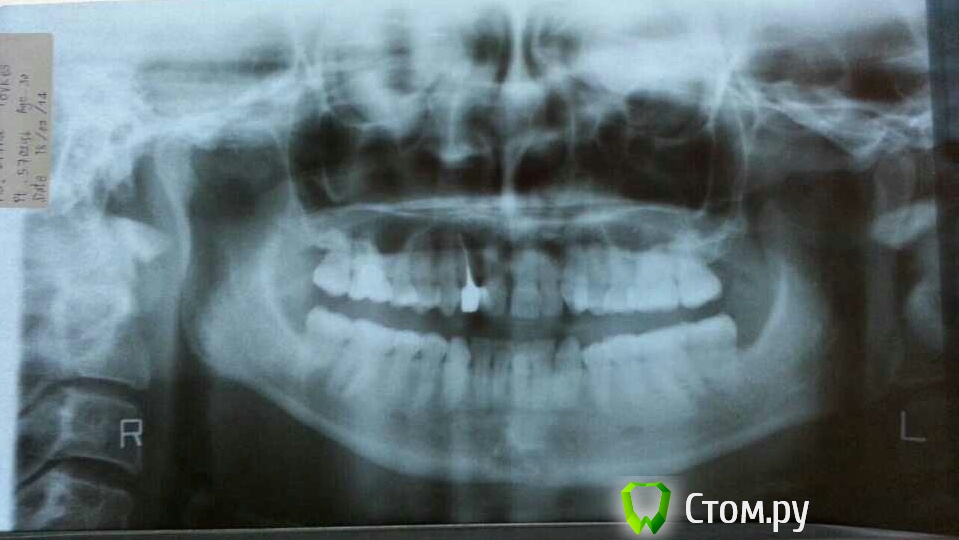

Ярка Опубликовано 18 февраля, 2014 Автор Поделиться Опубликовано 18 февраля, 2014 выложите панорамный снимок (ОПТГ) сегодня появилась возможность сделать панорманый снимок Ссылка на комментарий

IvanK Опубликовано 17 февраля, 2014 Поделиться Опубликовано 17 февраля, 2014 Здравствуйте,выложите панорамный снимок (ОПТГ) Ссылка на комментарий

Ярка Опубликовано 17 февраля, 2014 Автор Поделиться Опубликовано 17 февраля, 2014 выложите панорамный снимок (ОПТГ) Я узнаю о такой возможности тут. Если будет возможность - сделаю. 1 Ссылка на комментарий